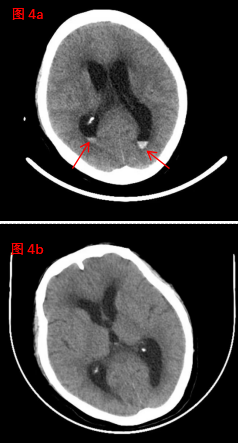

在神經(jīng)外科與腎病科的通力協(xié)作和精心救治下,患者精神狀態(tài)逐漸改善、飲食睡眠不斷好轉(zhuǎn),住院40天后,恢復(fù)良好,復(fù)查顱腦CT(圖4b)較入院時(圖4a,紅色箭頭處指示顱內(nèi)血腫)明顯吸收。患者行走自如,滿意出院!(神經(jīng)外科、宣傳科)